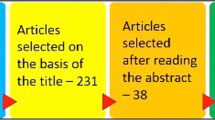

A total of 30 MultiNeO CS (Control group- CG) and 30 MultiNeO NH CS (Test group- TG) implants were inserted in 36 patients. Table 1 summarizes the main characteristics of the patients for both treatment groups. Tables 2 and 3 summarize the main clinical and radiographic results of the two groups of implants.